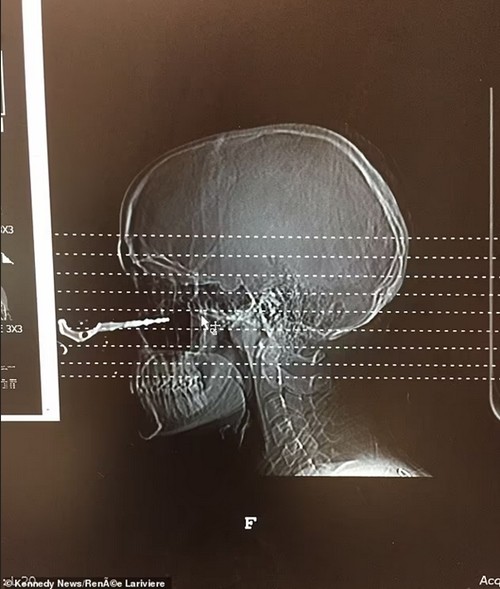

Người bạn lập tức gọi cấp cứu và Renée được đưa vào bệnh viện. Việc chụp X-quang cho thấy chiếc chìa khóa ghim sâu khoảng 2,5cm vào khoang mũi của Renée. Đến các bác sĩ và y tá cũng ngạc nhiên trước tai nạn này. Thậm chí, một bác sĩ trong phòng cấp cứu còn xin phép chụp một tấm ảnh của Renée để cho các sinh viên y khoa xem.

Phim chụp cho thấy chìa khóa ghim vào khoang mũi của Renée. Ảnh: Renée Lariviere.